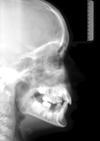

Die Fernröntgenseitenaufnahme dient der Analyse der Lage des Gebisses im Schädel. Die Auswertung wird in unserer Praxis mit Hilfe eines Computers vorgenommen.Die Fernröntgenseitenaufnahme dient der Analyse der Lage des Gebisses im Schädel. Die Auswertung wird in unserer Praxis mit Hilfe eines Computers vorgenommen.